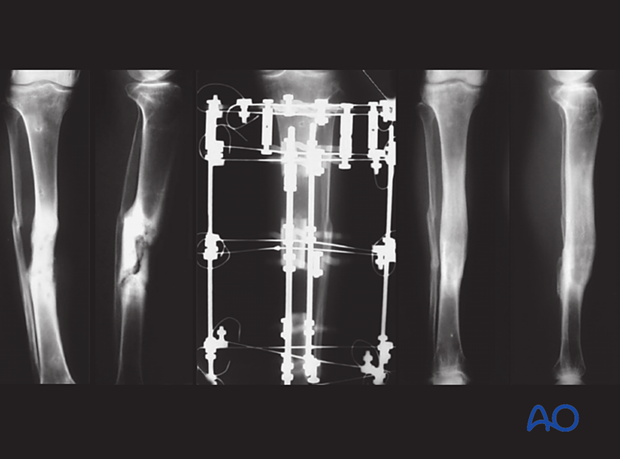

If a fracture has become infected, it requires debridement and fixation with either an external or internal fixator. The illustration on the left demonstrates proper external fixation placement.

The details of external fixation must include planning for wound care and preserving access for flap coverage. Additionally, fixator configuration should ensure excellent stability.

An external fixator can be used as a temporary, or a definitive stabilizer. Even if external or internal fixation will be used definitively, it may be best to use a temporary fixator after initial debridement. This aids repeated debridement and wound care. Once further wound access is unnecessary, a new fixation construct that provides optimal stability can be applied.

This illustration shows the results of incorrect and correct insertion of screws/pins for external fixation. A complex fracture caused by direct trauma is shown.

External fixation is a means of stabilization in infected fractures and nonunions. It provides stability without the need for implants inside the infected wounds.

In septic surgery, external fixation may need to remain for up to a year, or more. It may be necessary to replace one or more pins during the course of treatment. There are three basic systems:

All three systems have advantages and disadvantages. External fixation with Schanz pins is the simplest option and is very adaptable. The ring fixator is the most complicated system but can be used for compression and lengthening. A hybrid frame is simpler than a ring fixator and tensioned wires may have fewer pin-related problems.

These fixators must provide stability as in any other fracture fixation situation. If there is a problem with stability (loosening or infection) then the fixator must be replaced.